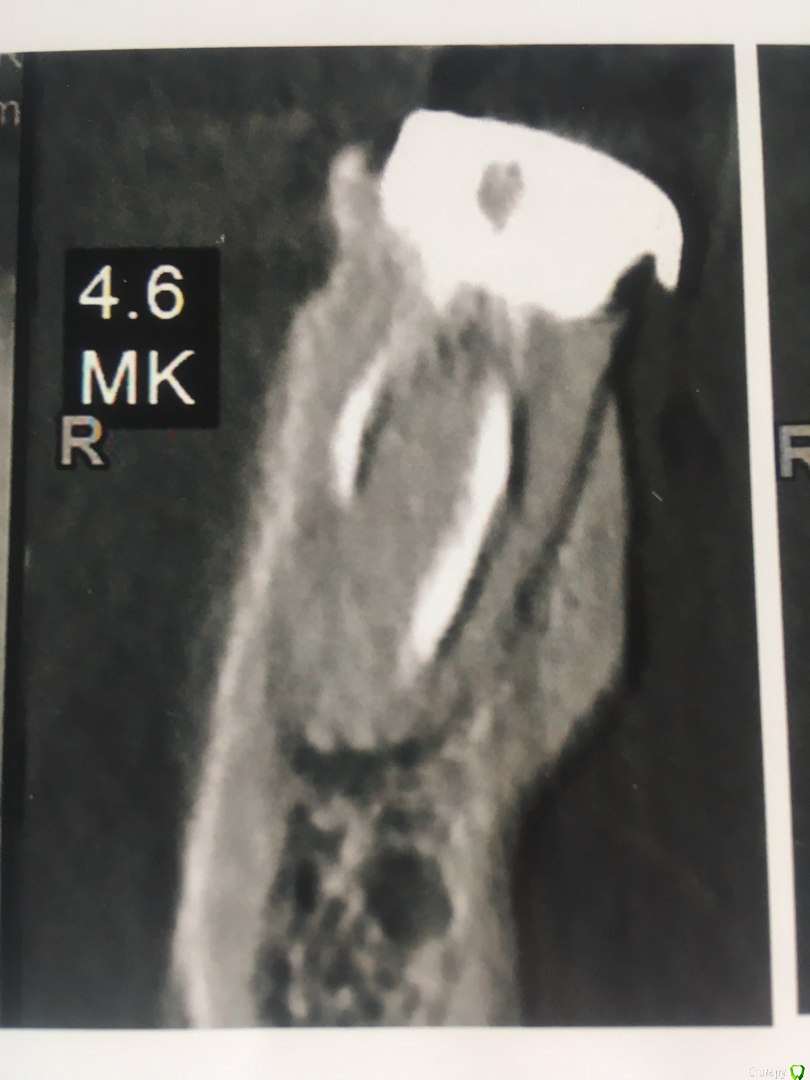

Коронковой части у зуба практически нет,только корень, поставлен штиф  и на него пломба в виде коронки зуба.

В течении  года от зуба опустилась десна и там проглядывается прозрачно-черный корень и очень быстро на 5 и 4-ки обазовались черные пятна.  Сделала КТ. Теперь стоит вопрос долгое  лечение или удаление.Врач говорит все будет видно при вскрытии. Если лечение то долгое и без гарантий.   Мне кажется от корня там мало что осталось,судя по цвету и по тому как быстро испортились рядом стоящие зубы. Может проще не лечить,установить имплант?

Правда один врач сказал,что то вроде убыли костной ткани и имплант удержать будет не чем,кроме того сужение верхней челюсти, рецессия десны и стирание в пришеечной области из за прикуса. В заключении кт -пародонтопатия легкой степени тяжести.

Добрый вечер!  Благодарю за ответ. Побывала у другого врача. Мнения разошлись. Второй доктор сказал 4,6  удаляем, а верхний 2,6 лечим.Первый же доктор сказал наоборот. Можно спросить еще Ваше мнение по 2,6 и 2,5 зубам?)